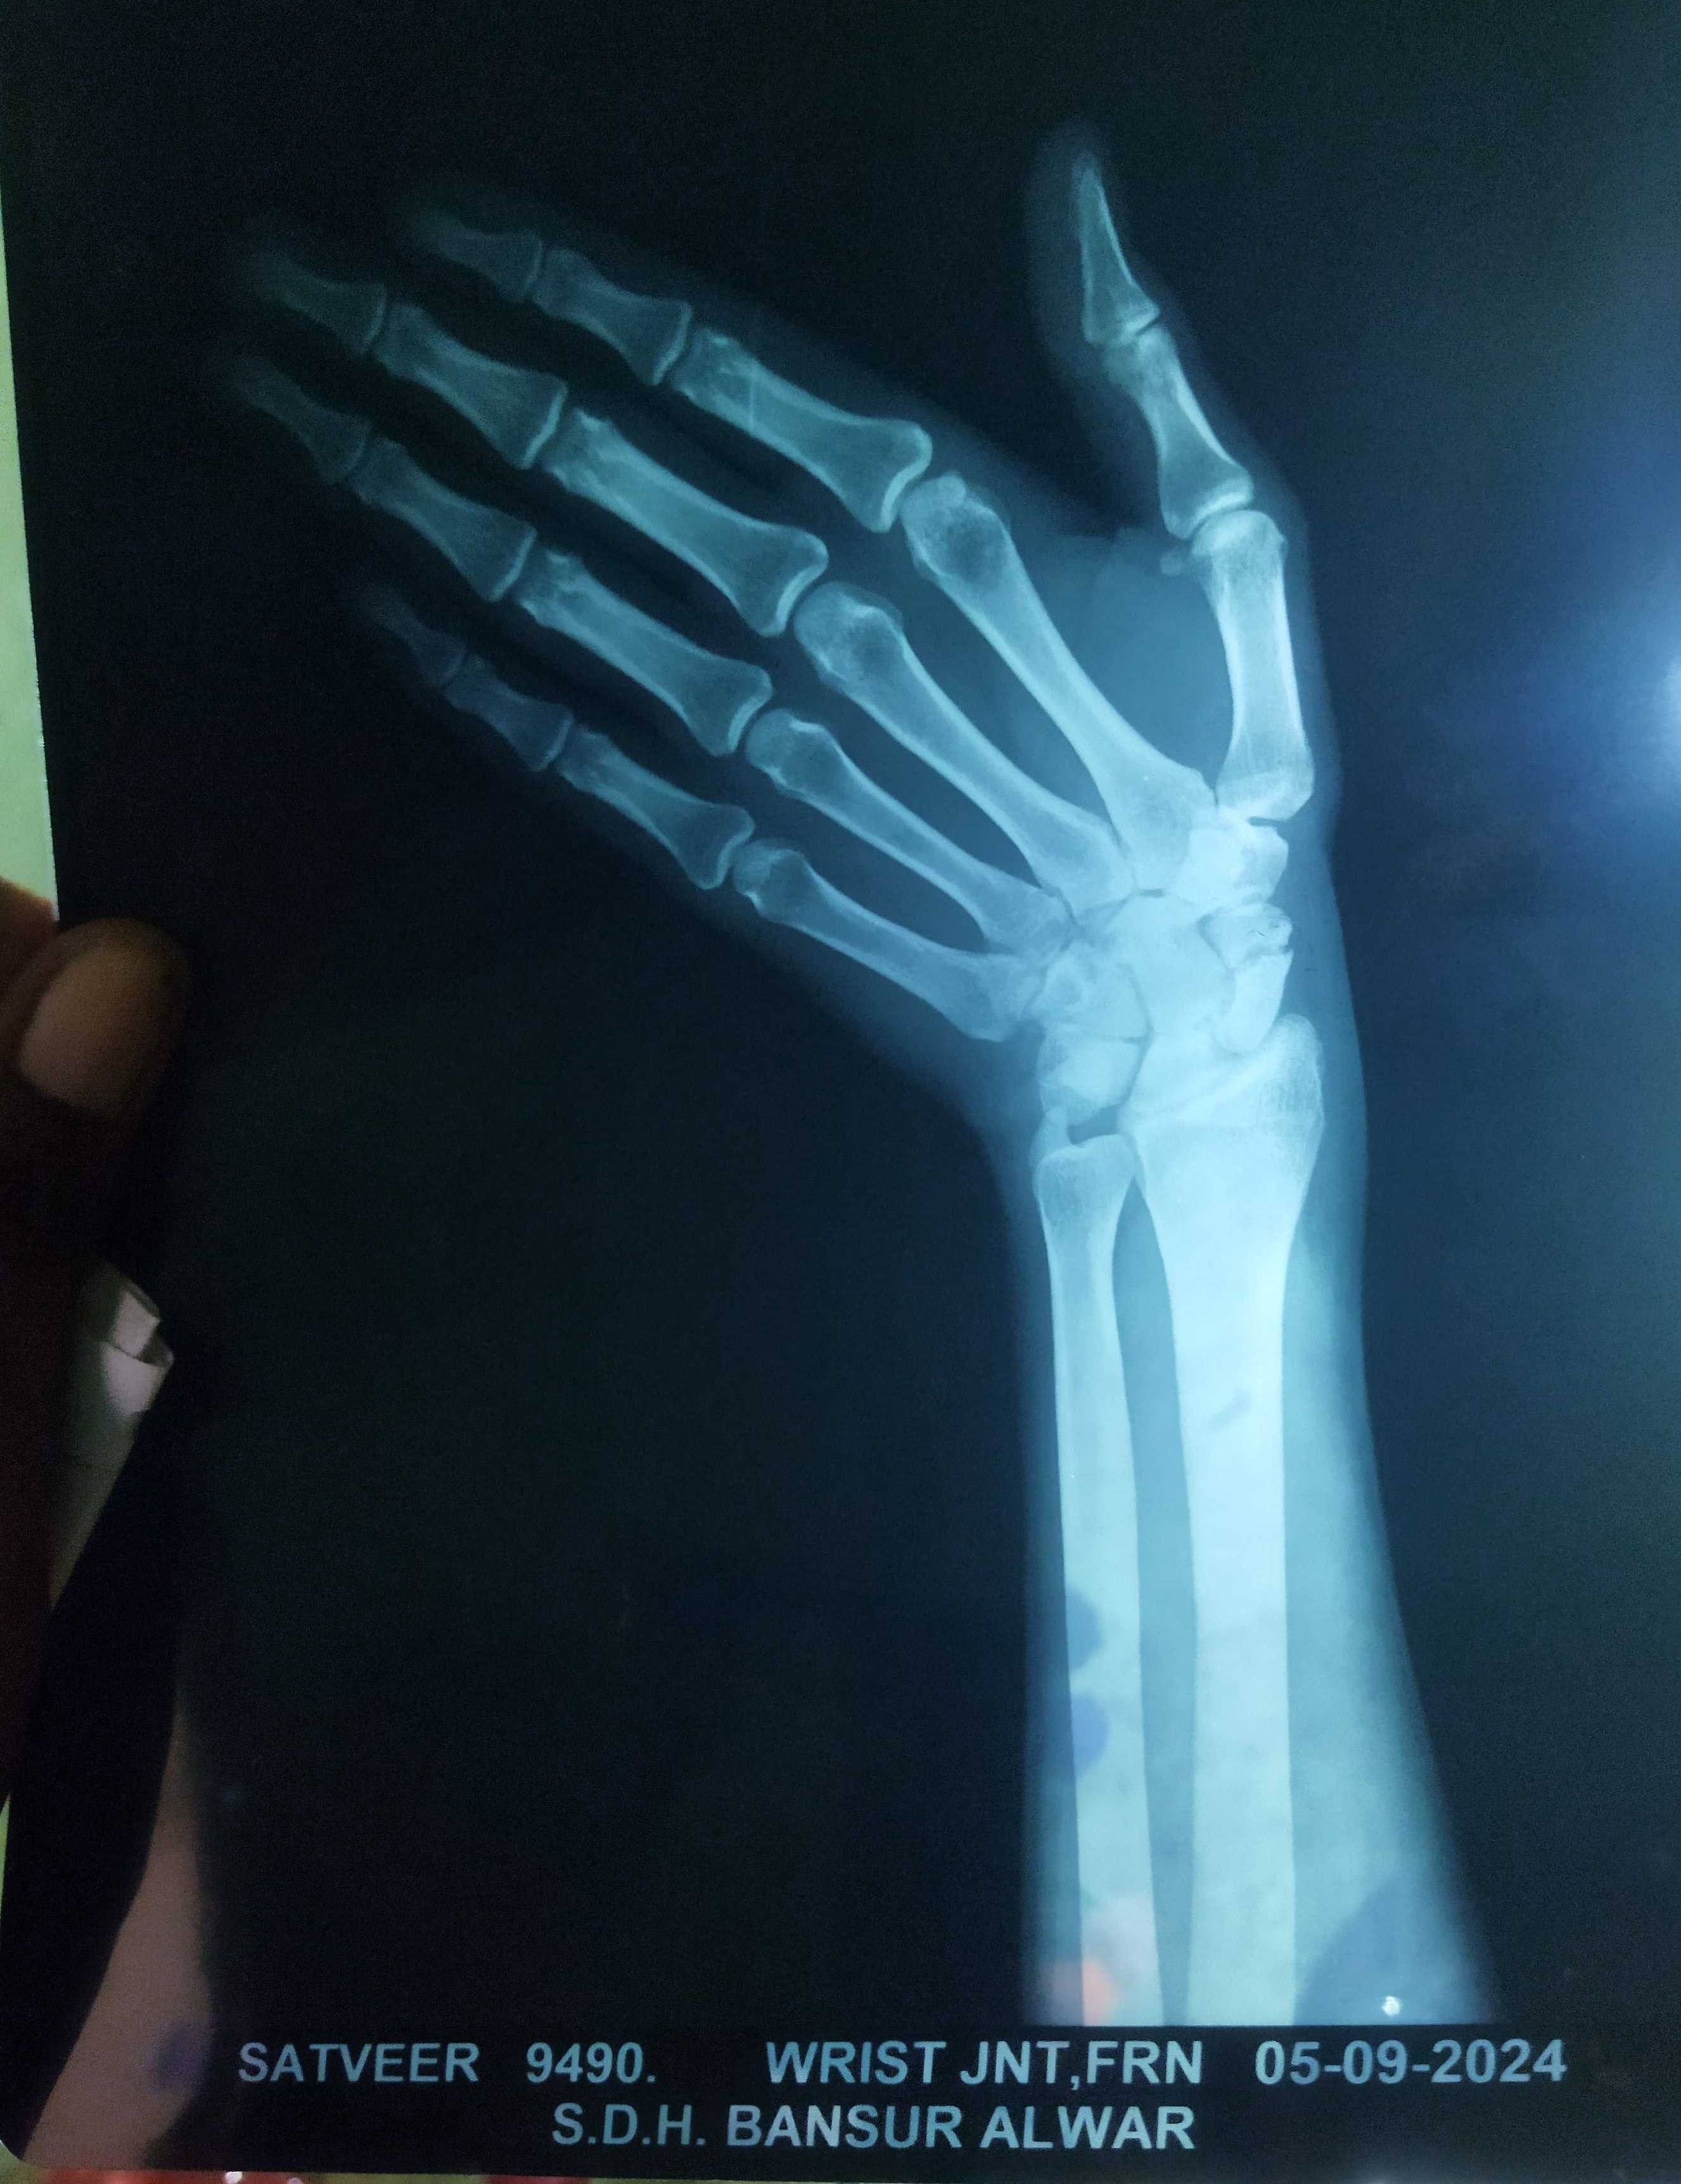

sachpoid fecture

mere left hand me scaphoid fecture hu ha 1 month ho gaya hai please suggest me treatment 1 month se plaster laga ha lakin nahi juda hai